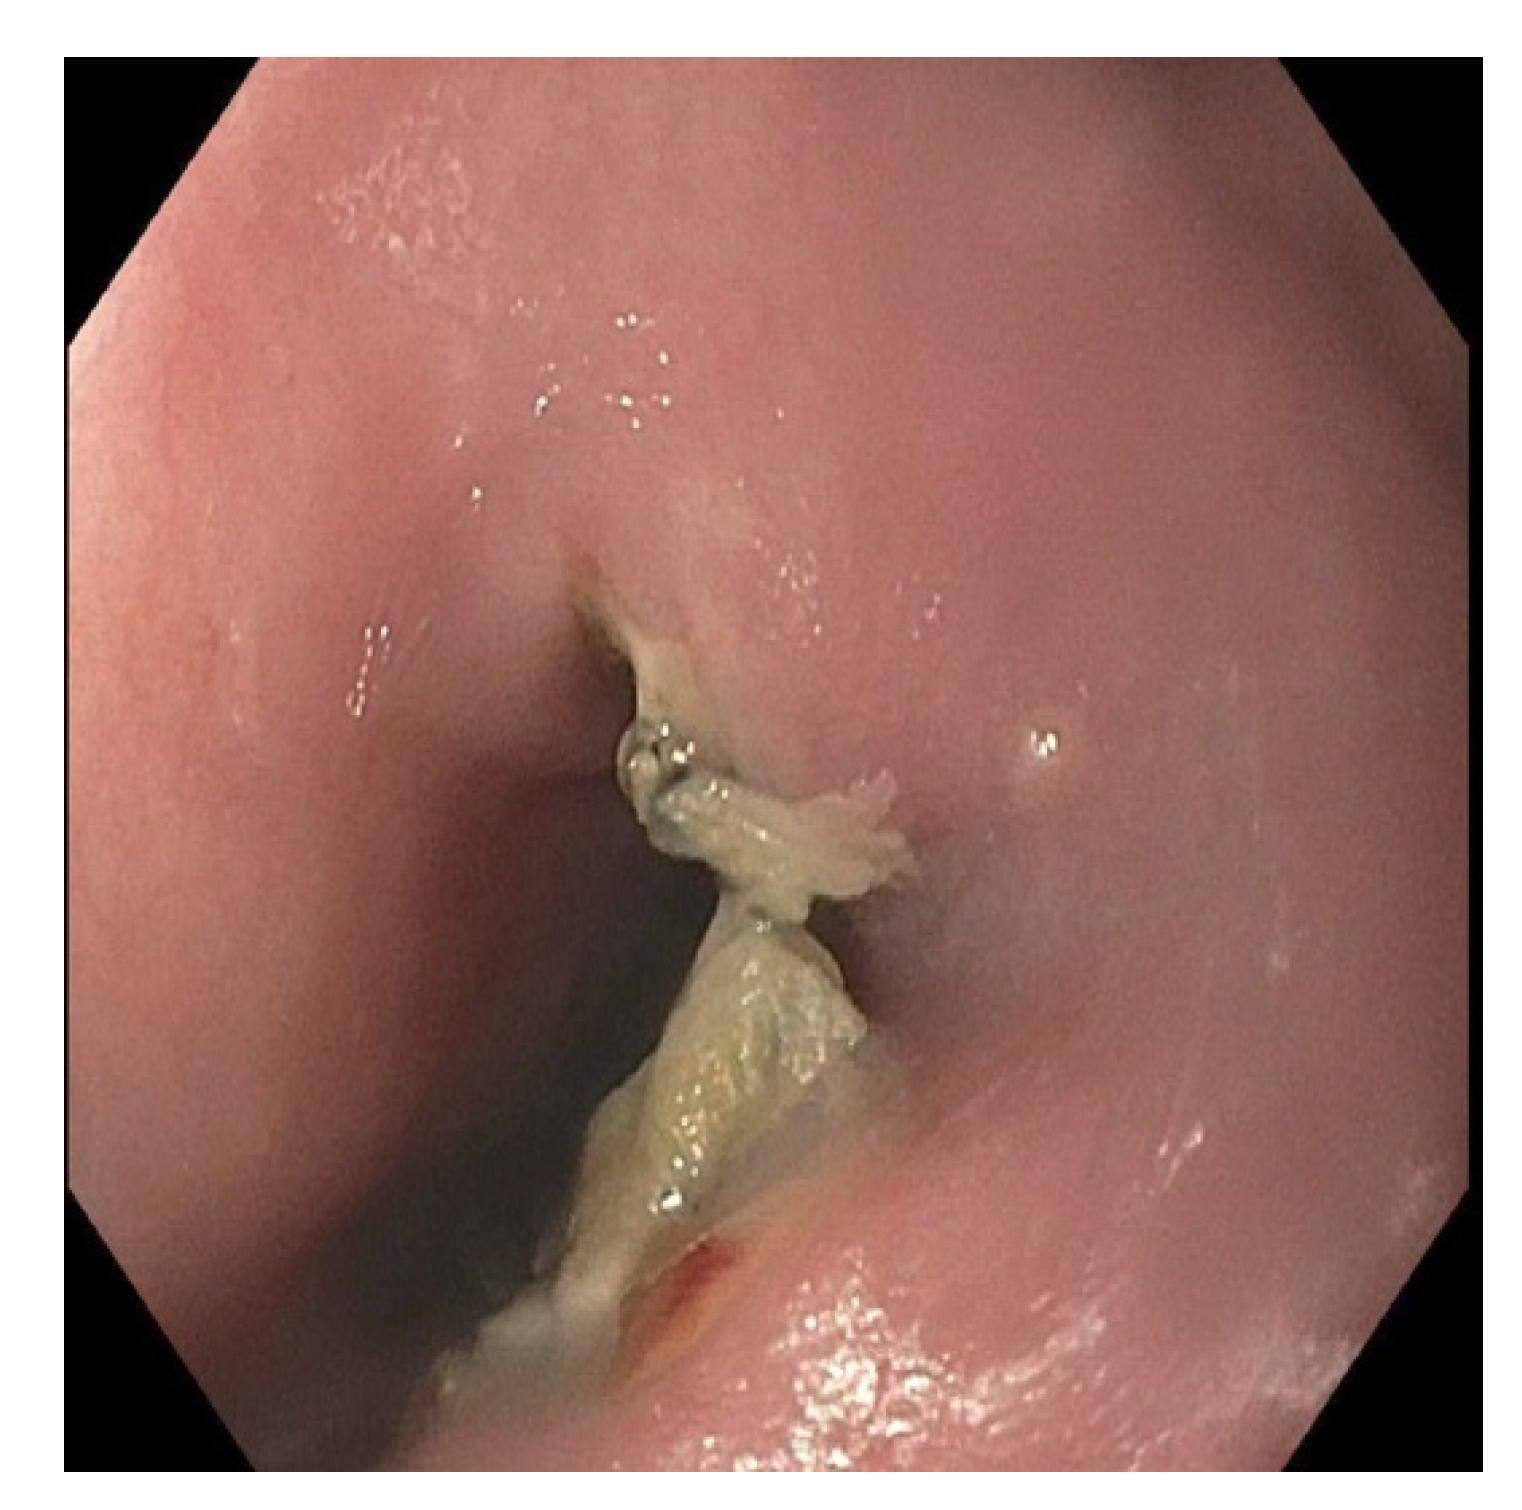

2. Case Presentation